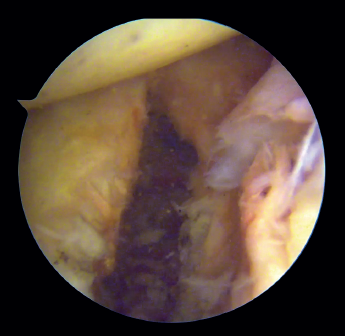

Preparation of the joint (Figure 1)

The patient is placed in lateral decubitus or beach chair position, depending on the preferences of the surgeon. A complete arthroscopic exploration is made through three standard portals, and the lesions are identified. The labrum and anterior capsule are then detached from the 2 to the 6 o'clock position, taking care to preserve their continuity. It is important to perform carefully detach labrum from the glenoid rim and remove all soft tissue until de muscle fibres of the subscapularis muscle and base of the coracoid are visualised. This will make easier the introduction of the graft and the creation of a flat bony surface to accommodate the graft.

Figure 1. View from the anterosuperior portal (left shoulder). Note the flat glenoid surface after drilling and roughening of the glenoid bed and deinsertion of the anteroinferior capsulolabral complex.

We then address the bone defect: with the glenoid defect exposed, the defect is evened, with drilling and roughening of the glenoid cavity neck until a flat and uniform surface is obtained on which to position the graft. The central point of the defect is selected for positioning of the graft, and an implant is inserted as a reference that subsequently will be used for capsulolabral repair.